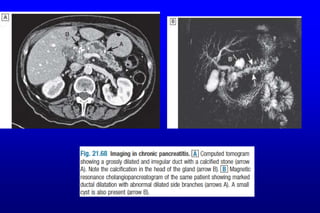

Chronic pancreatitis: Investigations

 Aims:

 Make a diagnosis of chronic pancreatitis

 Define pancreatic function

 Demonstrate anatomical abnormalities prior to surgical intervention.

Chronic pancreatitis: Investigations Aims:  Make a diagnosis of chronic pancreatitis  Define pancreatic function  Demonstrate anatomical abnormalities prior to surgical intervention.